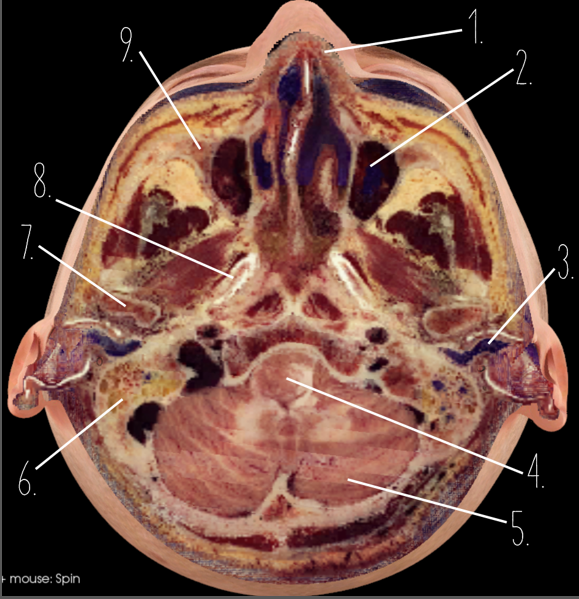

1?

Nasal Bone

2?

Maxillary Sinus

3?

External Acoustic Meatus

4?

Pons

5?

Cerebellum

6?

Mastoid Air Cells

7?

Mandibular Condyles

8?

Sphenoid Bone

9?

Maxillary Bone